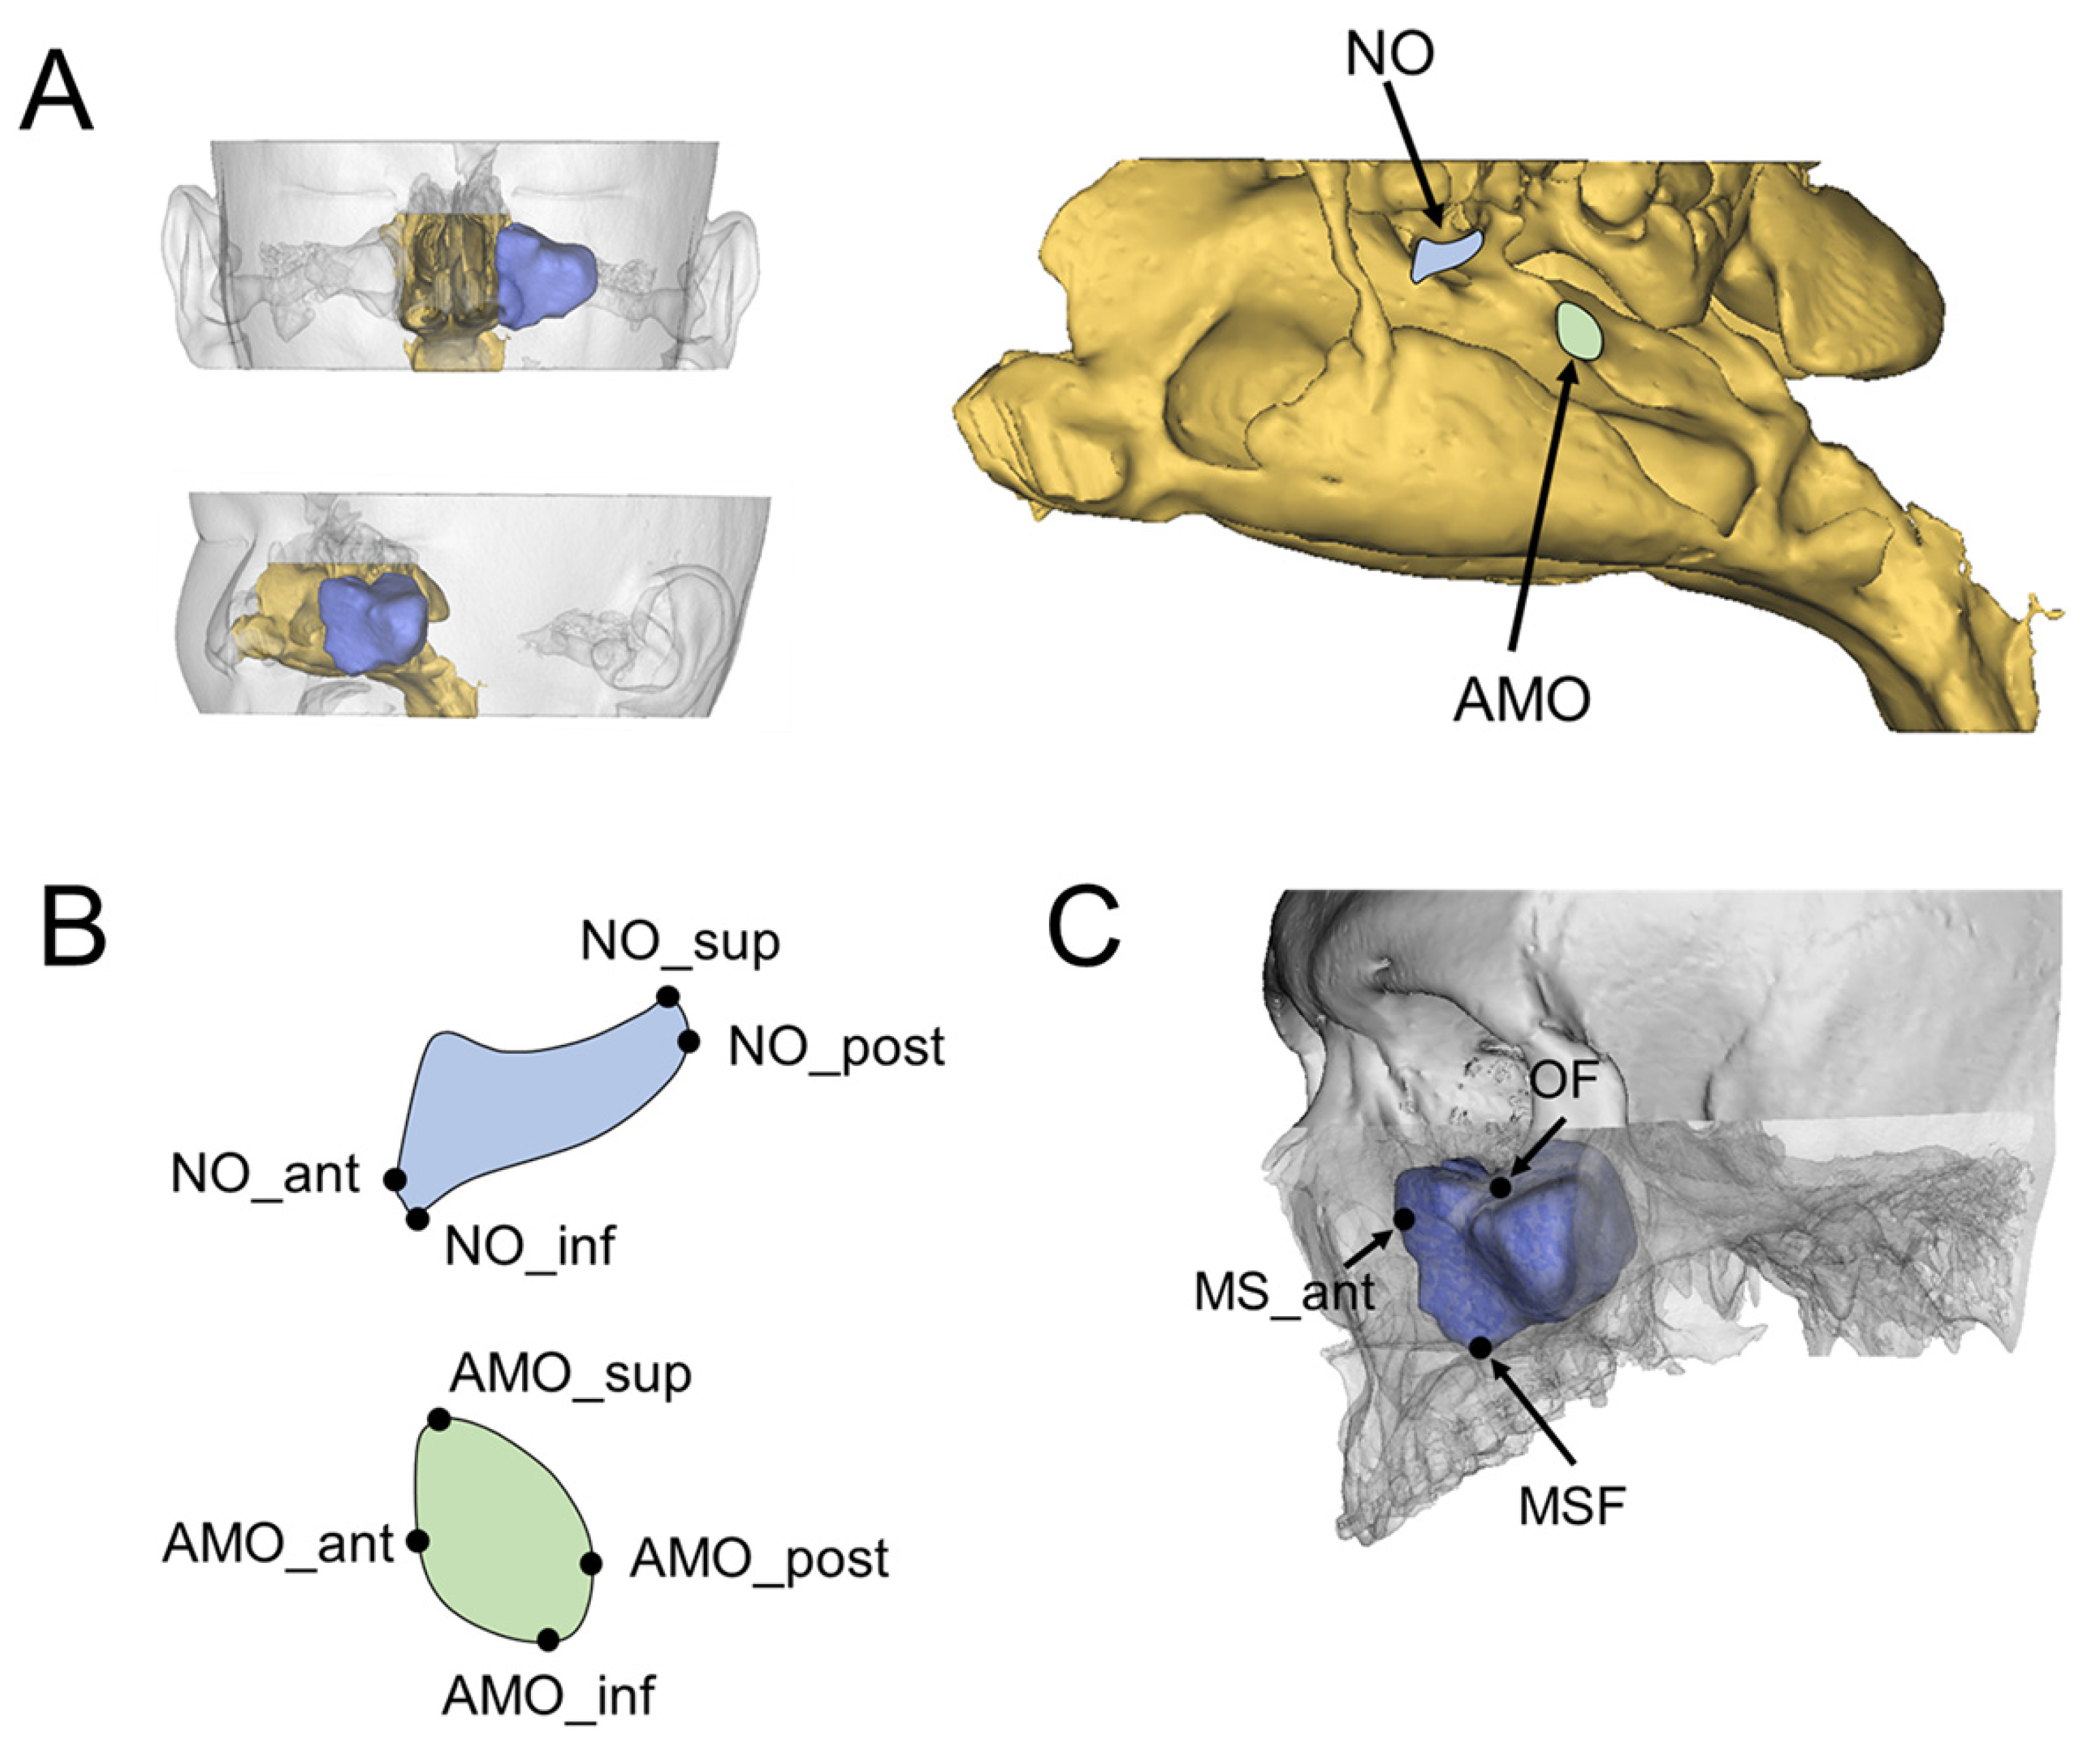

| Definition | |

|---|---|

| Landmarks | |

| AMO_sup | The most superior point of the AMO |

| AMO_inf | The most inferior point of the AMO |

| AMO_ant | The most anterior point of the AMO |

| AMO_post | The most posterior point of the AMO |

| NO_sup | The most superior point of the NO |

| NO_inf | The most inferior point of the NO |

| NO_ant | The most anterior point of the NO |

| NO_post | The most posterior point of the NO |

| MSF | The most inferior point of the maxillary sinus floor |

| MS_ant | The most anterior point of the maxillary sinus wall |

| OF | The most inferior point of the orbital floor |

| Location of AMO/NO | |

| AMO_AP location | Distance from the MS_ant to AMO_ant in the antero-posterior direction |

| AMO_SI location_inf | Distance from the MSF to AMO_inf in the supero-inferior direction |

| AMO_SI location_sup | Distance from the OF to AMO_sup in the supero-inferior direction |

| NO_AP location | Distance from the MS_ant to NO_ant in the antero-posterior direction |

| NO_SI location_inf | Distance from the MSF to NO_inf in the supero-inferior direction |

| NO_SI location_sup | Distance from the OF to NO_sup in the supero-inferior direction |

| Dimension of AMO/NO | |

| AMO_horizontal dimension | Distance from the AMO_ant to AMO_post in the antero-posterior direction |

| AMO_vertical dimension | Distance from the AMO_sup to AMO_inf in the supero-inferior direction |

| NO_horizontal dimension | Distance from the NO_ant to NO_post in the antero-posterior direction |

| NO_vertical dimension | Distance from the NO_sup to NO_inf in the supero-inferior direction |